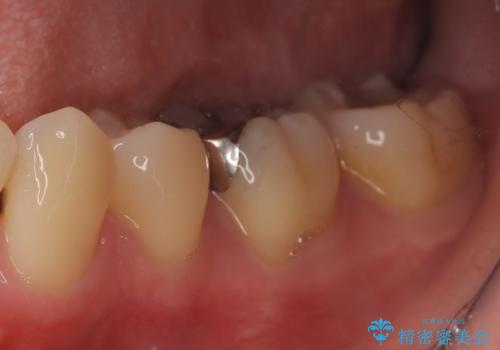

- 「銀歯を白くしたい」を主訴に来院された患者さんです。 左下6番に銀歯を被せてあり、一部分が欠けている状態でした。

銀歯と虫歯を除去しハイブリッドインレーで治療を行いました。

ハイブリッドインレーはセラミックと合成樹脂(プラスチック)が混ざったものです。従って経年劣化や色の変化はあるものの、保険適応の被せ物に比べ、セラミックの含有率が高く、型取りの材料もシリコン材を使用出来るので適合も優れています。